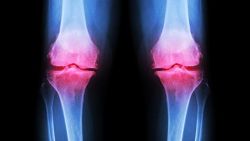

Thoái hóa khớp được chia thành hai loại: thoái hóa khớp nguyên phát và thoái hóa khớp thứ phát. Thoái hóa khớp nguyên phát xảy ra do sự hao mòn sụn không rõ nguyên nhân còn thoái hóa khớp thứ phát xảy ra do một bệnh lý khác.

Hiện tại không có cách nào có thể chữa trị khỏi hoàn toàn bệnh thoái hóa khớp và phục hồi khớp đã bị hỏng nhưng có nhiều phương pháp điều trị có thể giúp kiểm soát các triệu chứng.

Viêm khớp vảy nến (psoriatic arthritis) và thoái hóa khớp (osteoarthritis) là hai trong số những dạng viêm khớp phổ biến nhất. Thoái hóa khớp xảy ra do sự hao mòn khớp theo thời gian và đa phần xảy ra ở người cao tuổi trong khi viêm khớp vảy nến là một bệnh tự miễn có thể xảy ra ở bất kỳ độ tuổi nào.